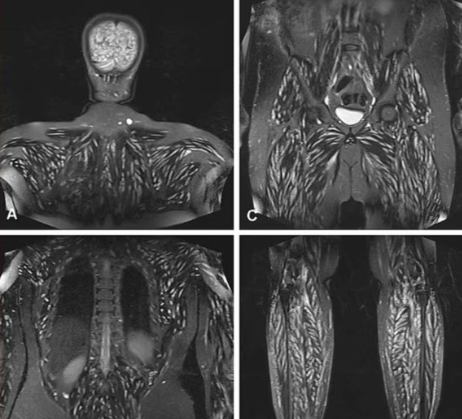

여성의 증상은 나아지지 않았다. 이를 두고 쉬 박사는 “낮 중에 갑자기 깨어나서 지난 몇 시간 동안의 일을 전혀 기억하지 못하는 경우도 있었다”고 말했다. 결국 의료진은 여성의 뇌 상태를 면밀히 관찰했다. MRI 검사 결과 목과 얼굴, 혀에서 이상한 반점이 발견됐다. 간과 척추 등 온몸 곳곳에서도 비슷한 병변이 관찰됐다.

![갈고리촌충으로 인해 목에 낭종이 생긴 사례 [사진출처=유튜브 Chubbyemu]](https://img3.daumcdn.net/thumb/R658x0.q70/?fname=https://t1.daumcdn.net/news/202410/20/akn/20241020134709563fjmq.jpg)

성의 몸에 소 촌충만 있는 것이 아니었다. 극심한 두통을 일으킨 것은 바로 돼지고기에서 흔히 발견되는 갈고리촌충이었다. 이 촌충의 알은 장에서 빠져나와 피부에 딱딱한 혹처럼 느껴지는 낭종을 형성한다. 유충은 일반적으로 해롭지 않지만, 뇌로 침투하면 두통과 발작 등 심각한 증상을 유발할 수 있다.